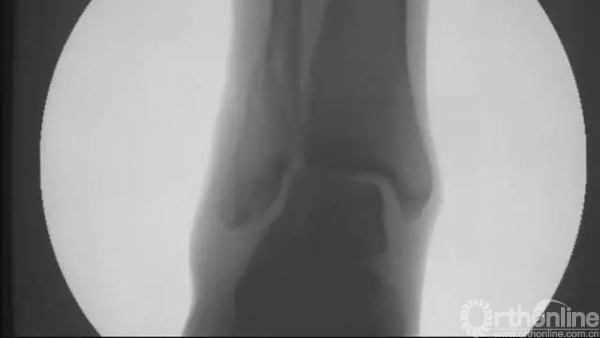

透视下复位良好

正侧位透视,髓内钉位置满意